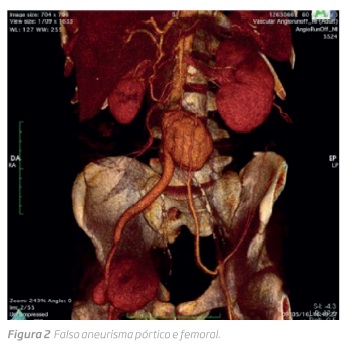

Permaneceu aparentemente assintomático até 2015 (6 anos pós operatório), altura em que se verificou a presença de tumefação inguinal direita, pulsátil, que motivou investigação clínica (figura 1). Após realização de angio-tomografia computorizada (TC) que mostrou falso aneurisma anastomótico femoral direito e aórtico (figura 2) foi submetido a bypass aortobifemoral com prótese de prata (Silvergraft).

Em Agosto de 2017 esteve internado em Medicina Interna por urosépsis com isolamento em hemoculturas de Escherichia coli multi-resistente tendo tido alta com antibiótico dirigido. Em 5 de Setembro 2017 é observado por tumefação inguinal bilateral e febre. Realizou angio-TC que mostrou infeção protésica, aposição da ansa duodenal D3 com provável fístula aorto-entérica e doença arterial obstrutiva com oclusão das artérias femorais superficiais. Foi feita drenagem de exsudado purulento (figura 3) em grande quantidade e iniciado antibiótico de alto espectro.